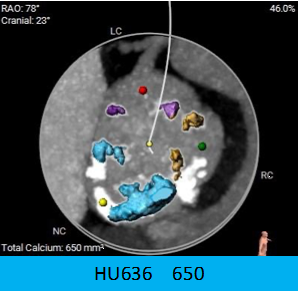

2.CT数据显示该患者为TYPE1二叶式主动脉瓣,重度钙化,钙化分布不均,钙化沿无冠瓣叶及管壁附着缘分布,左右瓣之间有黏连钙化。

3.左冠开口高度偏低,瓣叶较长,冠脉风险较高,右冠高度可。

1.TYPE1二叶瓣,重度钙化分布不均匀,存在瓣膜下移的风险,瓣周漏可能性较大。

2.术前CT影响评估显示:左冠开口高度为11.0mm,左冠瓣瓣叶长度为17.7mm,存在冠脉阻挡风险。

瓣环上解剖及钙化分布: